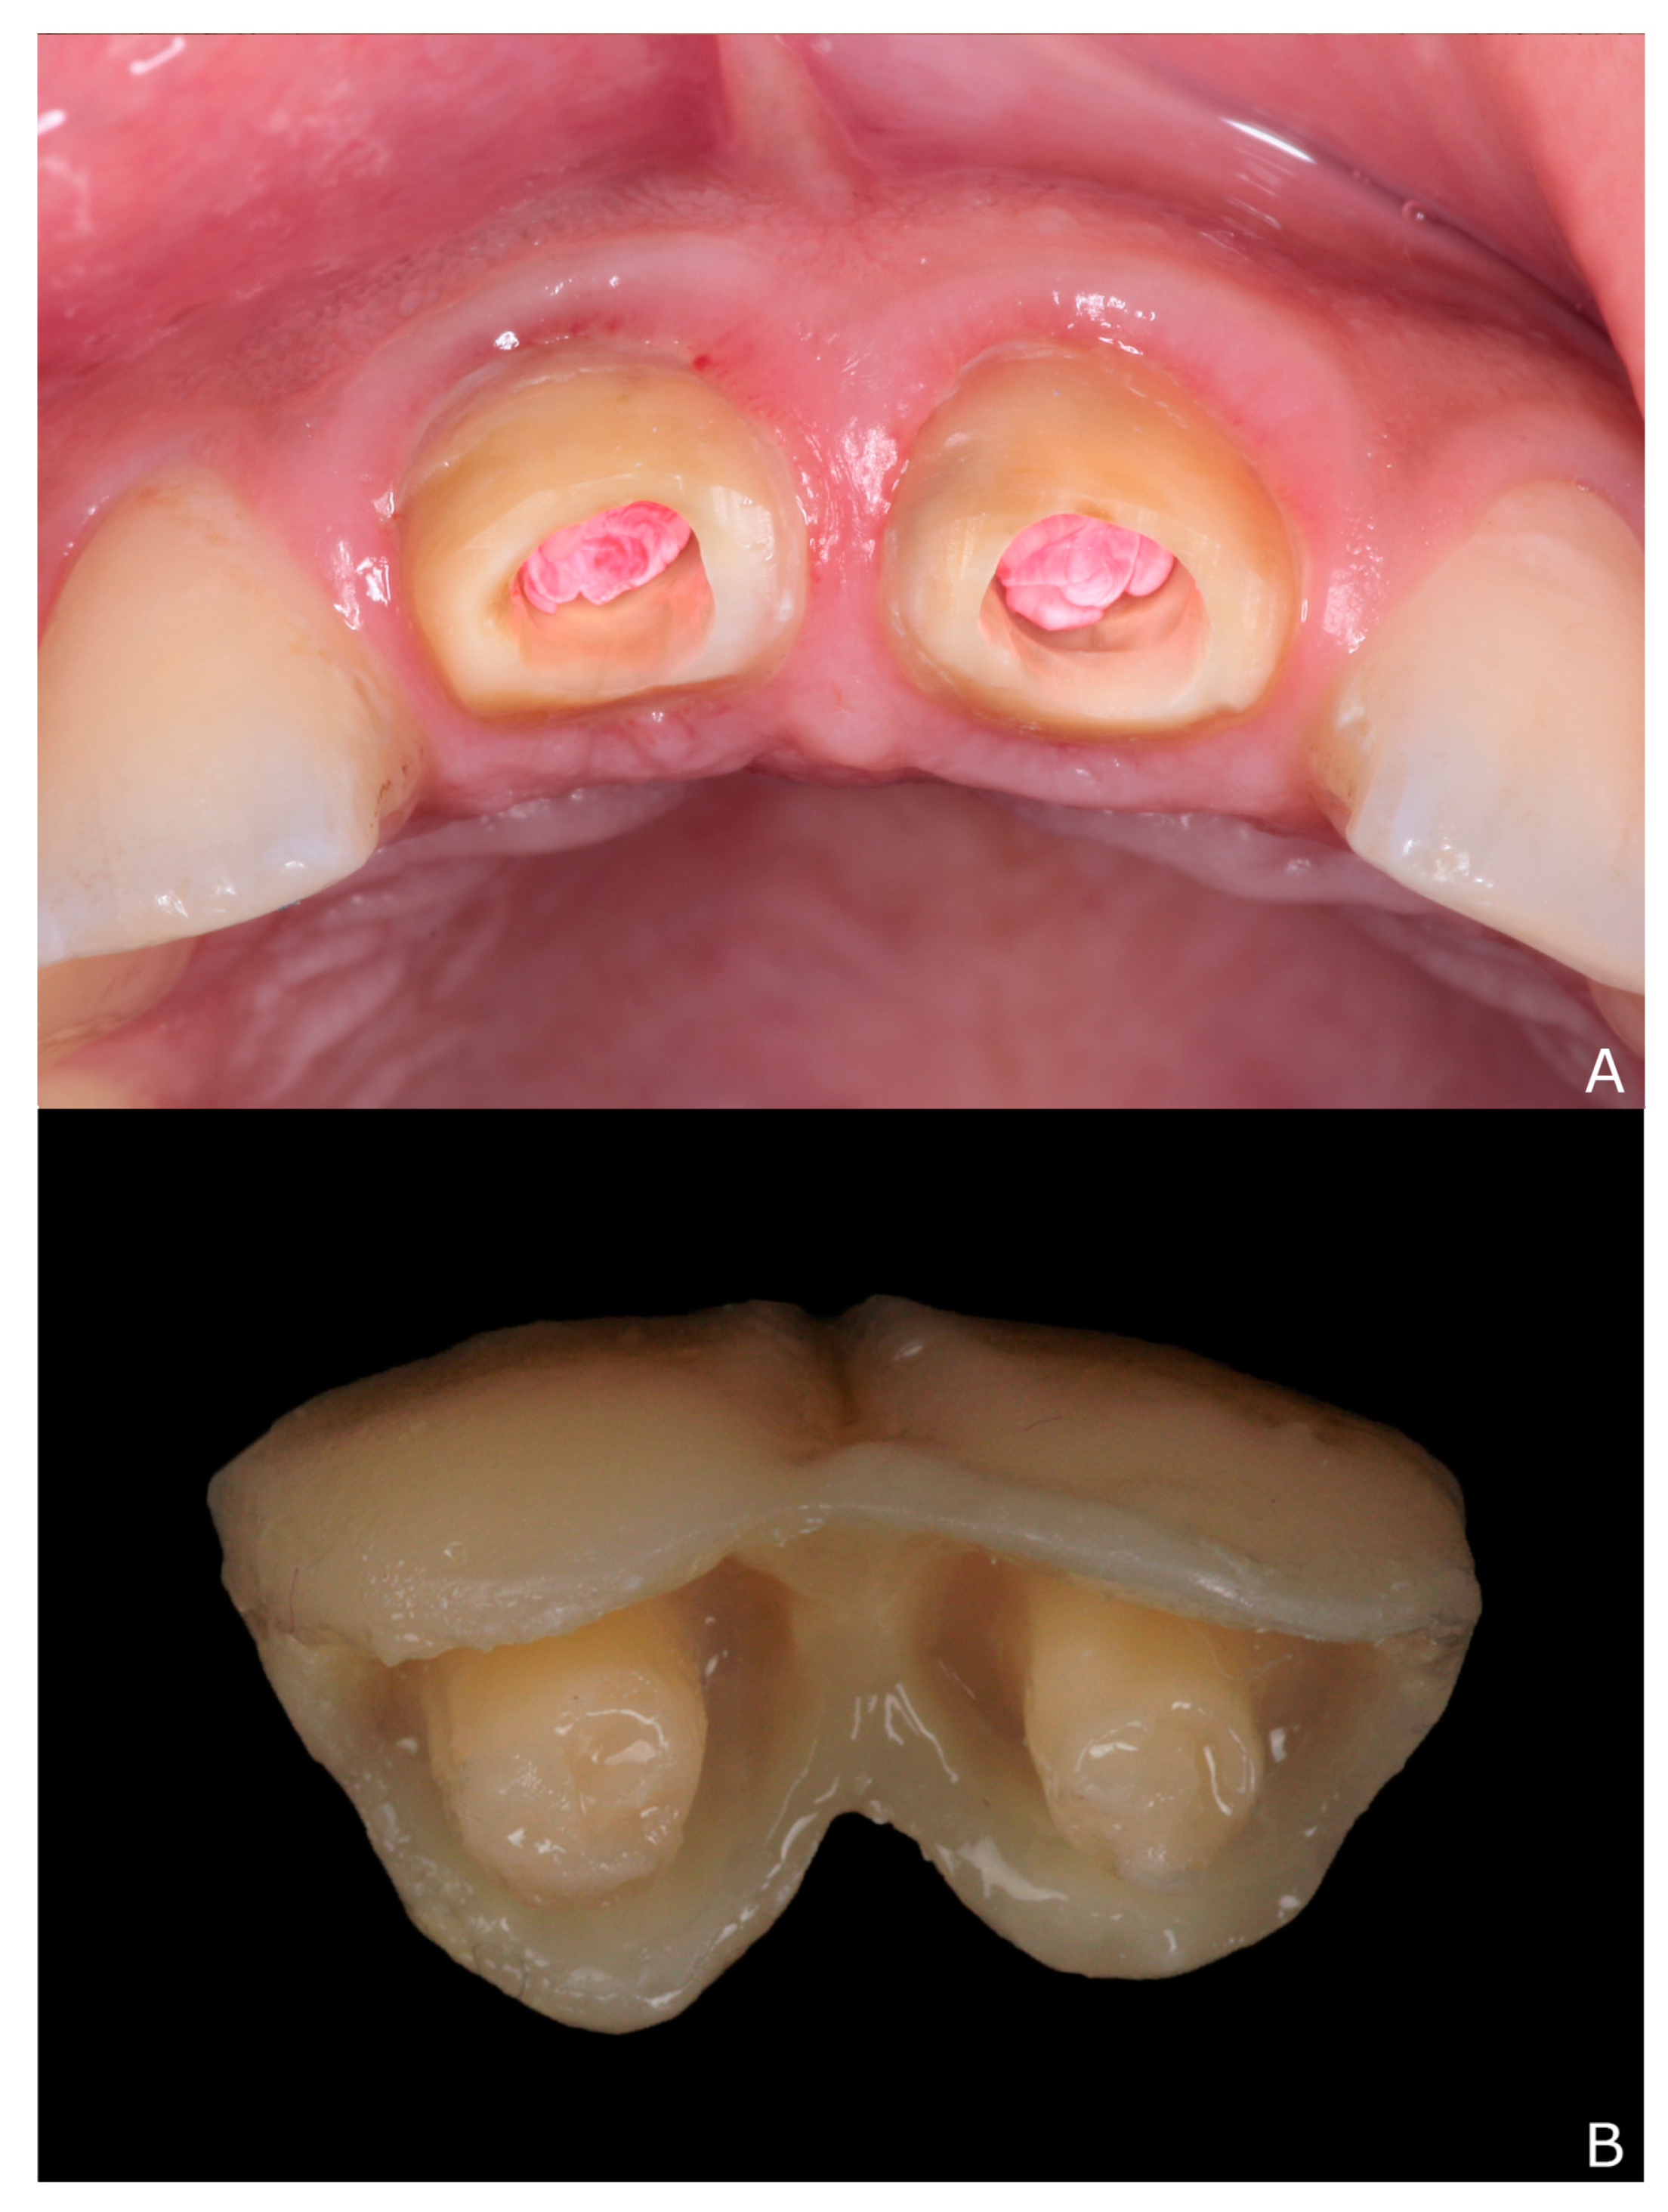

2. Clinical Report